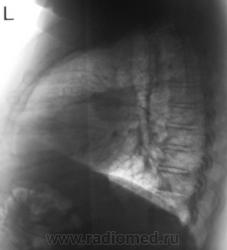

Начало 2008 года. При расшифровке флюорограмм, пациента "взяли на контроль", заподозрили периферический рак левого лёгкого (по "прямой" флюорограмме). Вроде-бы все правильно и логично?

В апреле 2009 года пациент пришел "для динамического наблюдения" - серия 2.

После повторного дообследования (апрель 2009 г) - 2 серия изображений, мы были твердо уверены, что пациент взят на учет..., но не тут-то было. В пятницу рентгенолаборант флюорографа попросил подойти и "глянуть снимок"...

Оказывается "данный" пациент направлен для прохождения профилактической флюорографии..., так как надо было поменять водительские права...?

Вот флюорограммы.

2. Конечно, мы на свой страх и риск, произвели дообследование, согласно стандарту. Итог дообследования представлен в серии 3.